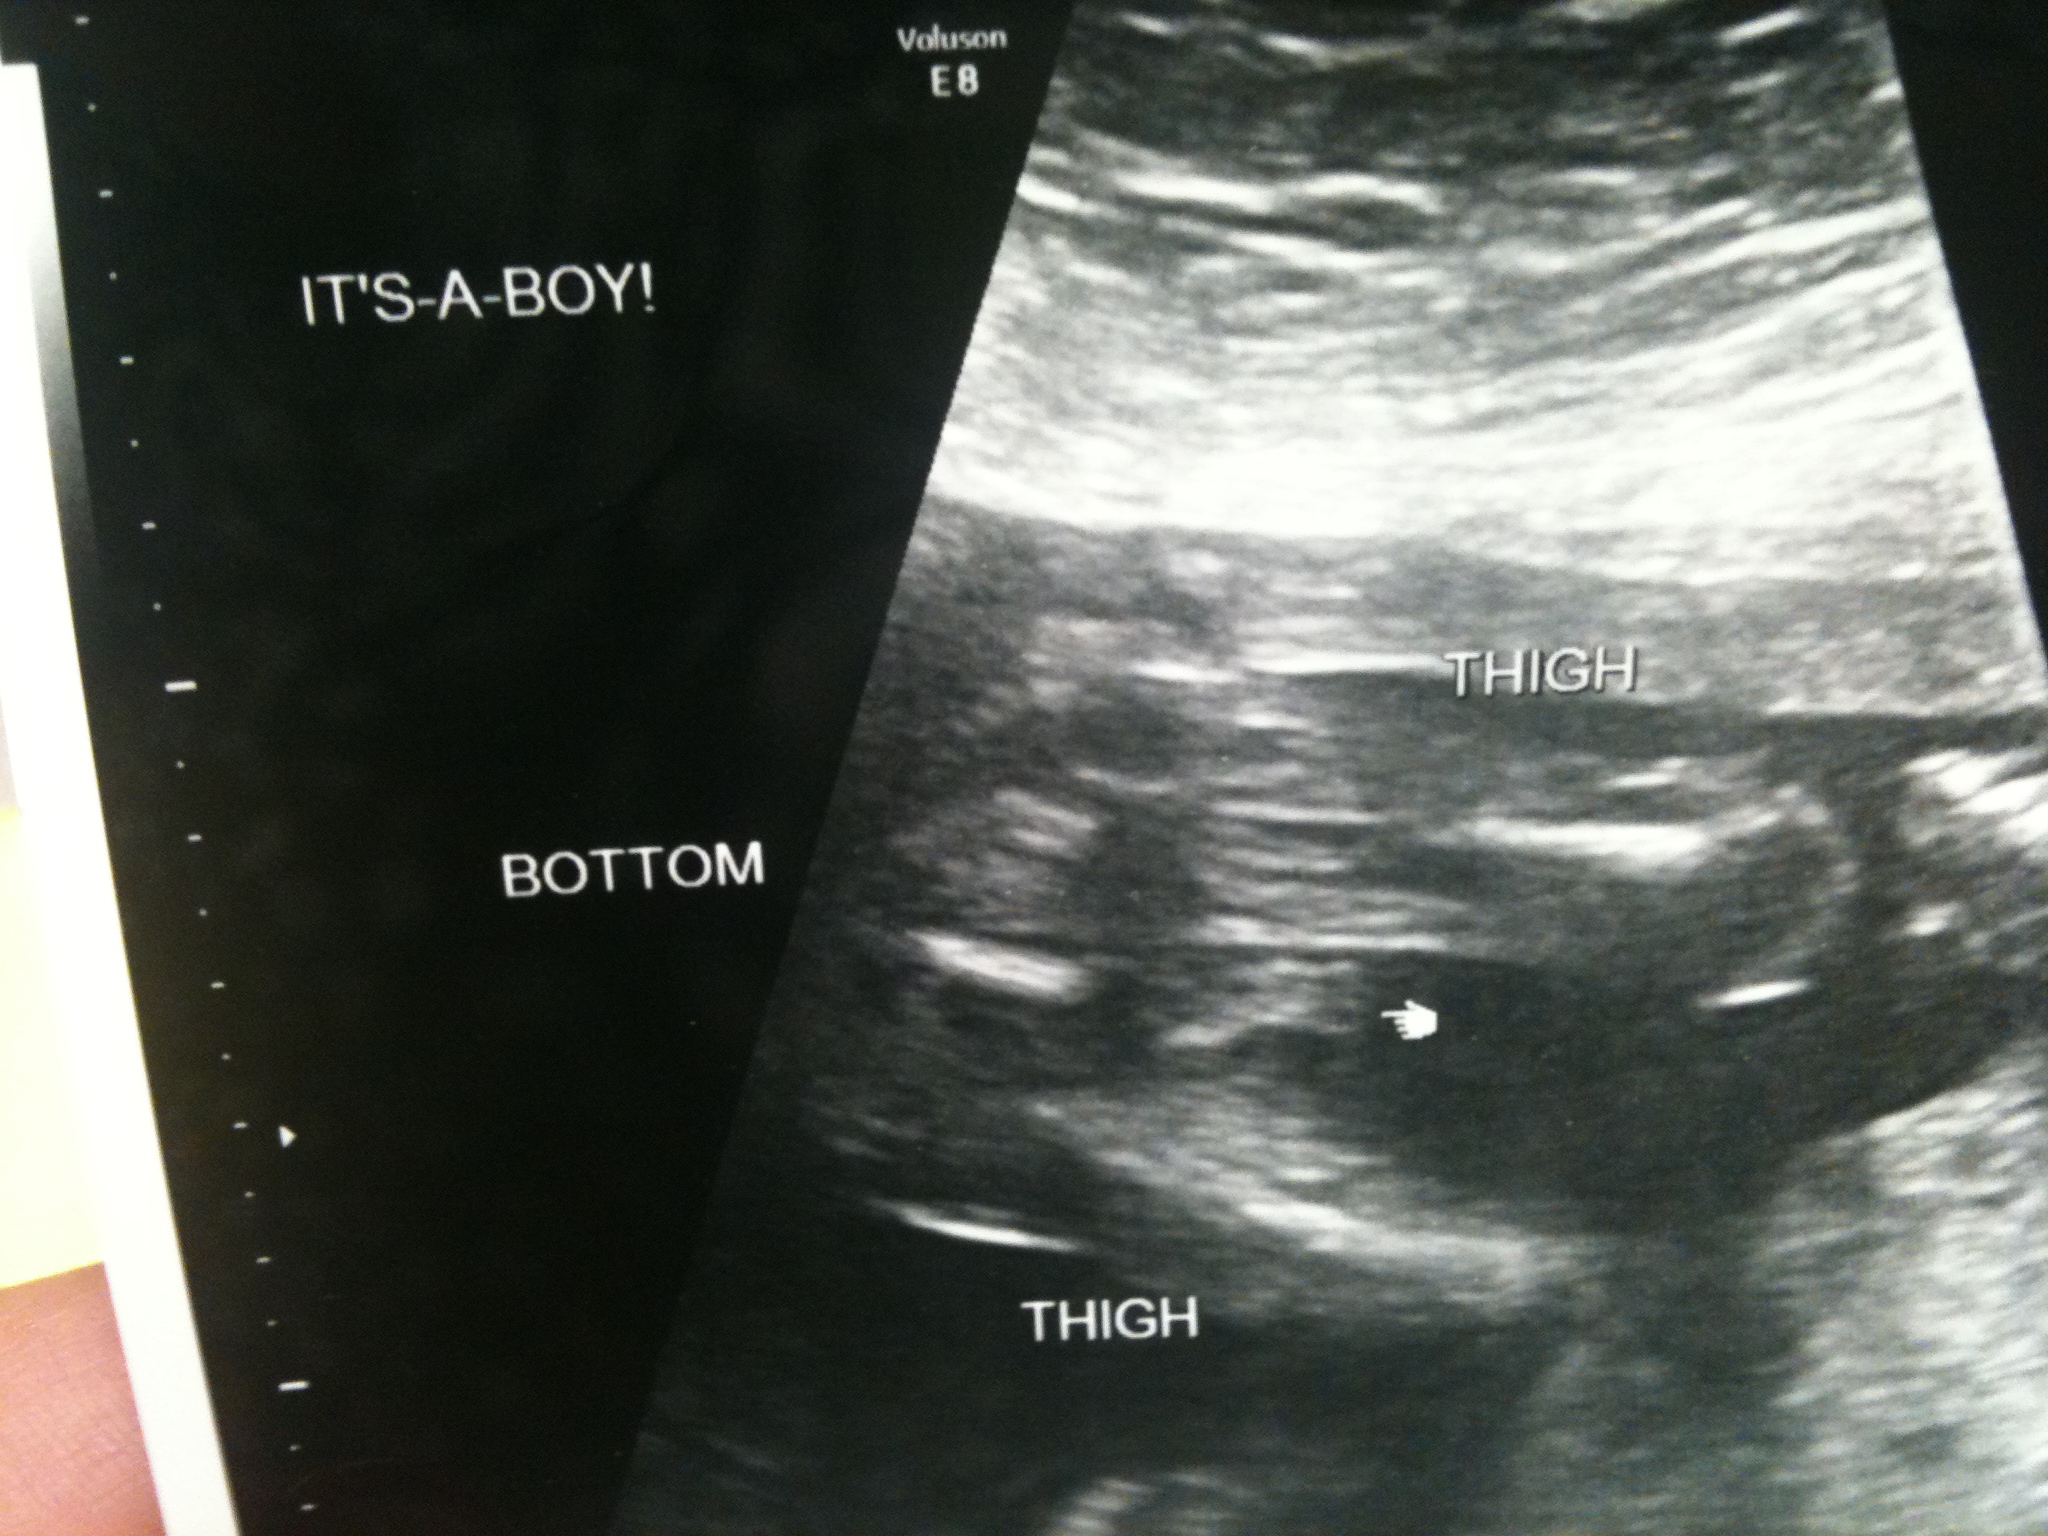

Well, we went in for our appointment today, and we definitely found out your sex! 🙂 I am super excited! Jack didn’t want to know until after school today since we weren’t sure if we’d be back from the doctor before he went to kindergarten. Another reason why he chose to wait was so that Grandma Holly wouldn’t be the last to find out you were a boy, since she was kind of bummed she was one of the last ones to find out about you in the first place (but that was because we wanted to tell her in person!)